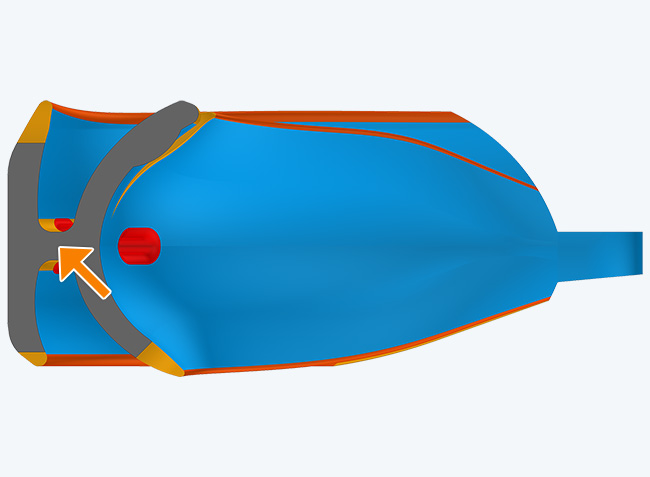

The TMJ Appliance®, which does not require any special fitting, is designed to act as an initial diagnostic and treatment tool for TMJ disorder. It works by decompressing the temporomandibular joint (TMJ), helps to correct mouth breathing and tongue posture habits, as well as limits bruxing. The TMJ Appliance® achieves TMJ disorder symptom relief immediately by alleviating pressure on the TMJ and relaxes the muscles around the jaw and neck.

The TMJ Appliance® treats both intracapsular and extracapsular disorders—TMJ clicking and pain (intracapsular) as well as pain referred from the craniomandibular muscles (extracapsular).